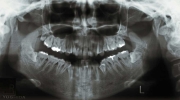

カテゴリー:ClassⅡ division 2 malocclusion (Overbite 5mm以上; 抜歯症例)

出題基準:大臼歯関係がclass Ⅱで、上顎中切歯1本を含む2本以上が舌側傾斜(U1-SN 90度以下)、犬歯関係もclass Ⅱであること。ただし、日本人では症例が少ないことを考慮して、U1-SN 100度以下のclass Ⅱ過蓋咬合も認める。抜歯・非抜歯は問わない。

出題の意味:このケースの条件は一般の人には理解しにくいところがある。通常出っ歯というと上の前歯が外に向かっていることを想像するのが普通であるが、U1-SNが90度以下というのは、上の前歯は内側に傾いていることを示している。なんで??。つまりこれは骨格性上顎前突と考えられるもので、上顎が歯並びごと全体が前へ出ていて、それだと上下の前歯があまりにも離れてしまうため、上の前歯が内側に倒れて下の前歯と何とか接触しようとしている状態と考えられる。

しかし、出題基準にも書いてあるように、このケースは欧米の白人によく見られるケースで、東洋人にはきわめて稀である。そこで類似ケースとして過蓋咬合(かがいこうごう)のケースを代替えとして認めるという配慮をしている。過蓋咬合とは非常に強く深く咬んでいる状態を言う。Overbiteとは前歯の垂直的な重なり具合を示す数値で、5mm以上だと上の前歯が下の前歯をほとんど覆い尽くしている感じになるので、前から見ると下の前歯はほとんど見えない状態になる。こういう状態が典型的な過蓋咬合である。典型的なclassⅡ,division 2のケースは過蓋咬合を合併している。